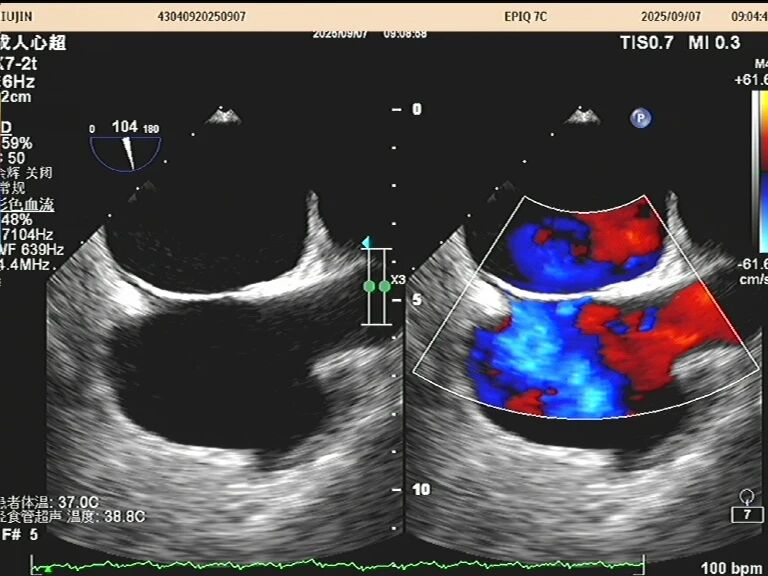

于是,一根如面条般柔软、顶端带着微型摄像头的探头,会从您的口腔缓缓进入食道。这个位置堪称完美,探头能紧贴着心脏,利用超声波为其拍摄一场无死角、超高清的“内部直播”。以前藏在背后的细微结构比如心耳里是否藏有血栓、人工瓣膜是否严丝合缝、心脏瓣膜上的小赘生物,此刻都一览无余。